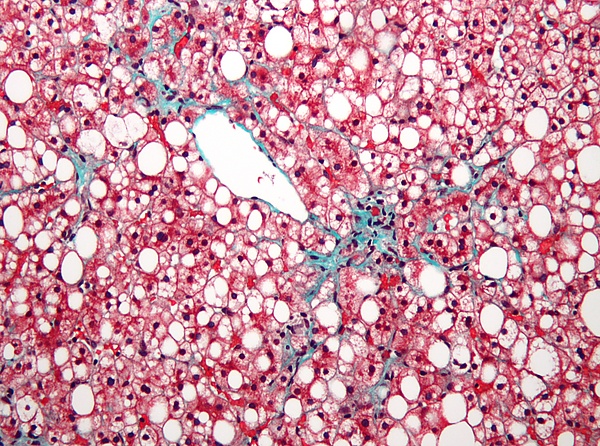

Неалкогольная жировая болезнь печени (НЖБП[источник не указан 2257 дней] или НАЖБП[2]) — частный случай стеатогепатоза, возникающего у людей, не злоупотребляющих алкоголем. Он связан с инсулинорезистентностью и метаболическим синдромом. Лечение включает в себя снижение веса, приём сахароснижающих препаратов (метформин, тиазолидиндионы)[3]. Неалкогольный стеатогепатит — наиболее тяжёлая форма НЖБП, приводящая к циррозу печени[4].